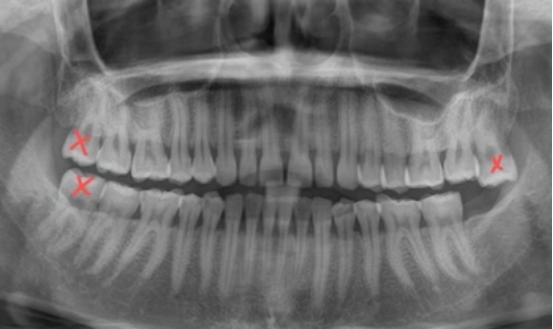

并非所有智齿都需要拔除。如果颌骨空间充足,智齿能完全、笔直地萌出,与对颌牙齿建立正常的咬合关系,它们就能像其他牙齿一样,正常发挥咀嚼功能。然而,现实中更多的情况是阻生——即智齿在萌出过程中因空间不足而受阻。根据生长方向,惹祸的智齿有不同“姿态”:

近中阻生:牙冠向前倾斜,直接顶住前方的第二磨牙,这是最常见的阻生类型;

水平阻生:牙齿完全“躺倒”,横向生长,对邻牙的压迫性最强;

2. 邻牙损害:尤其是前倾或水平阻生的智齿,其牙冠会持续顶撞、挤压前方的第二磨牙。这不仅可能导致第二磨牙牙根吸收、蛀牙,甚至造成邻牙松动。

面对智齿,我们无需过度焦虑,但应保持科学警惕。关键在于定期口腔检查,尤其是拍摄口腔X光片(如全景片),让牙医能清晰评估所有智齿的位置、形态及其与邻牙、神经管的关系。